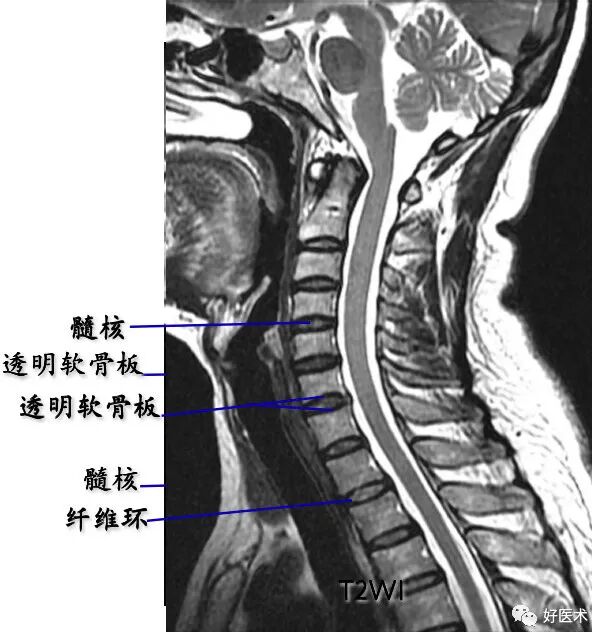

脊髓:位于椎管中心呈中等信号影

脑脊液:

T1WI上呈低信号;

T2WI上呈高信号影。

脊神经根:中等信号条状或圆点状影。

椎间盘:呈软组织密度影,CT值为70±5HU,不能区分髓核和纤维环

髓核:T2WI上呈较高信号

纤维环:T1WI和T2WI上均显示为低信号

sharpey纤维:T1WI和T2WI上均显示为低信号

透明软骨板:T1WI和T2WI上均显示为低信号